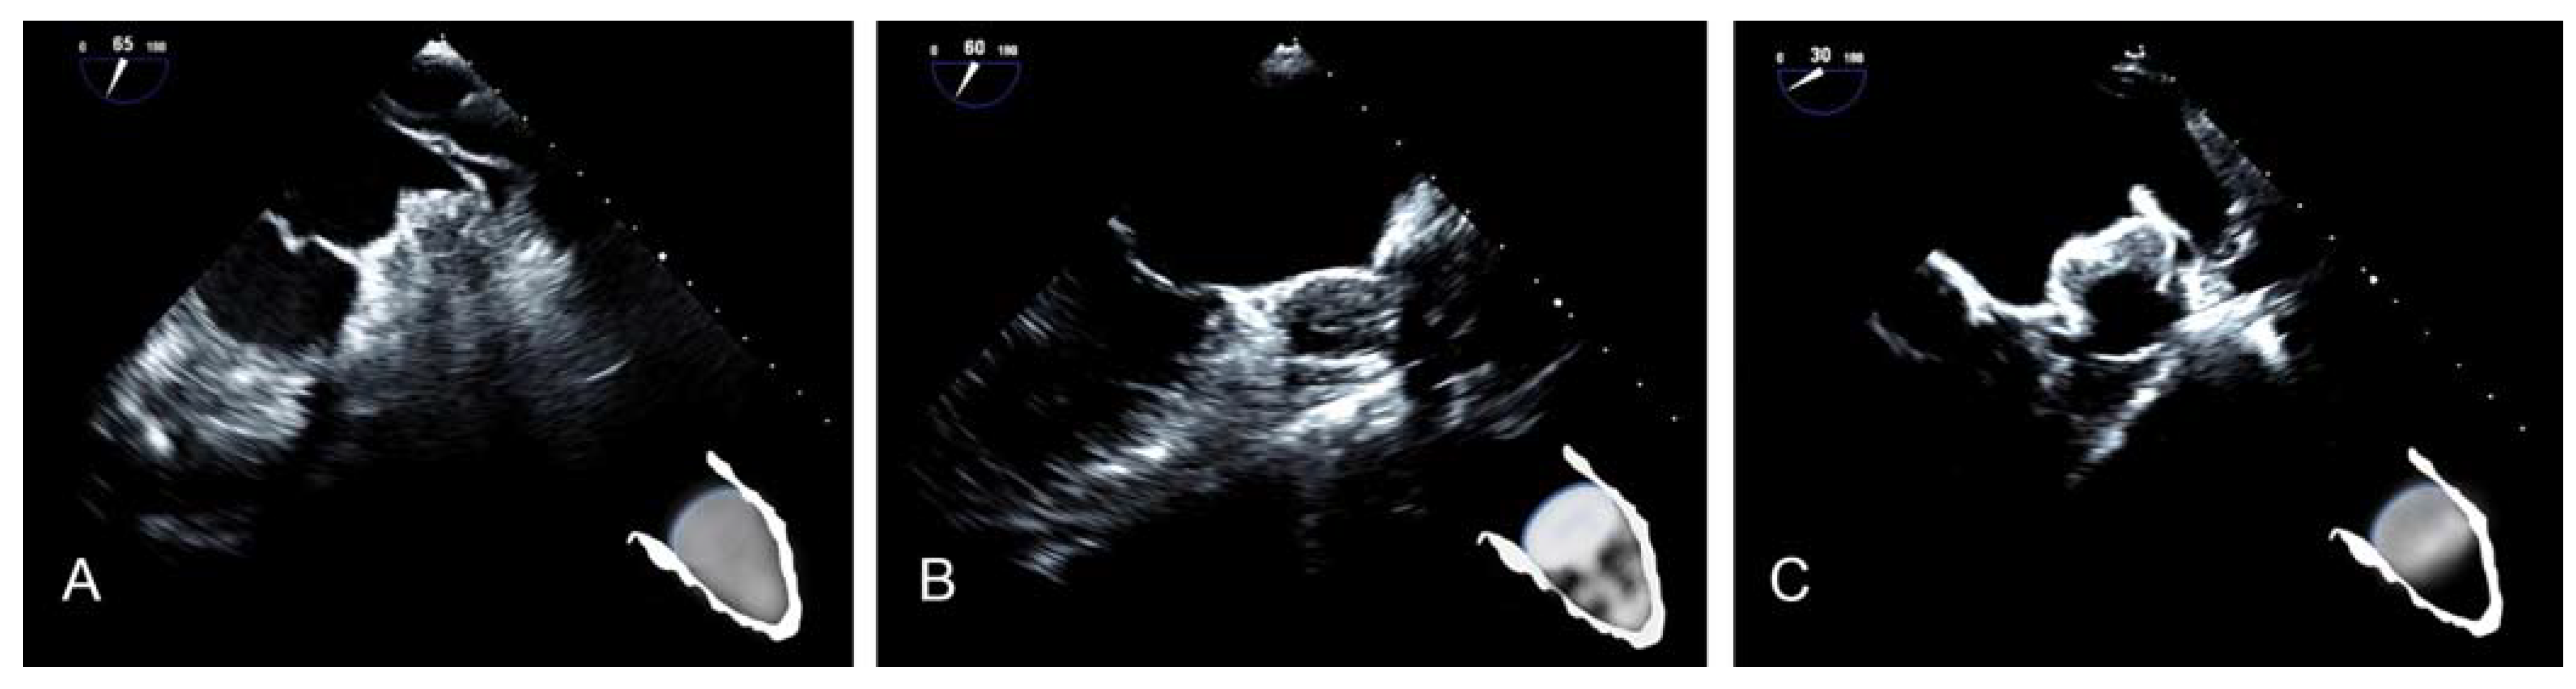

2.2. Echocardiographic Morphology after LAAO

- Hamadanchi, A.; Ijuin, S.; Haertel, F.; Bekfani, T.; Westphal, J.; Franz, M.; Moebius-Winkler, S.; Schulze, P.C. A Novel Echocardiographic-Based Classification for the Prediction of Peri-Device Leakage following Left Atrial Appendage Occluder Implantation. J. Clin. Med. 2022, 11, 1059. [Google Scholar] [CrossRef]